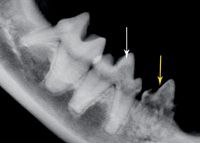

Photo 2: The right mandibular fourth premolar, tooth 408 (white arrow), has a subtle crown lucency but an intact periodontal ligament space surrounding the roots consistent with Type 1 tooth resorption. The third premolar, tooth 407 (yellow arrow), has more pronounced crown lucency and no discernable periodontal ligament space surrounding the roots, which is typical of Type 2 tooth resorption.

Type 2 (Photos 2 and 3) tooth resorption is generally thought to start at the apical half of the root. Crown involvement is generally not noted until late in the resorption process. The hallmark of Type 2 resorption is the lack of radiographic evidence of a periodontal ligament space surrounding the root.